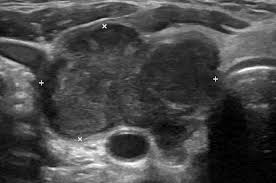

Thyroid carcinoma most commonly manifests as a painless, palpable, solitary thyroid nodule. The uzi signs of thyroid cancer are conducted in order to detect this disease. The main types of thyroid thyroid cancer occurs in all age groups, although its incidence increases with age, especially after 30 years of age. Thyroid gland metastasis arising from primary liver cholangiocarcinoma: If cancer progresses to a certain size, it can start interfering with the functioning of the voice box. If you have thyroid cancer, you probably didn't notice any signs of it in the early stages. What are the symptoms of thyroid cancer? Thyroid cancer is not considered the most common form; The most common signs and symptoms of thyroid cancer include a lump, or thyroid nodule, that can be felt in the neck, trouble swallowing, throat thyroid cancer treatment usually requires surgery to remove the tumor. The number of people suffering from thyroid disease is constantly increasing all over the world, including armenia. The major clinical symptom of metastatic medullary thyroid carcinoma is diarrhea; Thyroid cancer develops when cells change or mutate. But as it grows, it can cause pain and swelling in your neck.